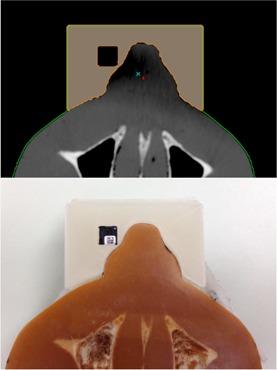

The purpose of this paper is to demonstrate that an inexpensive 3D printer can be used to manufacture patient-specific bolus for external beam therapy, and to show we can accurately model this printed bolus in our treatment planning system for accurate treatment delivery. Percent depth-dose measurements and tissue maximum ratios were used to determine the characteristics of the printing materials, acrylonitrile butadiene styrene and polylactic acid, as bolus material with physical density of 1.04 and 1.2 g/cm3, and electron density of 3.38 × 10²³ electrons/cm3 and 3.80 × 10²³ electrons/ cm3, respectively. Dose plane comparisons using Gafchromic EBT2 film and the RANDO phantom were used to verify accurate treatment planning. We accurately modeled a printing material in Eclipse treatment planning system, assigning it a Hounsfield unit of 260. We were also able to verify accurate treatment planning using gamma analysis for dose plane comparisons. With gamma criteria of 5% dose difference and 2 mm DTA, we were able to have 86.5% points passing, and with gamma criteria of 5% dose difference and 3 mm DTA, we were able to have 95% points passing. We were able to create a patient-specific bolus using an inexpensive 3D printer and model it in our treatment planning system for accurate treatment delivery.

本文的目的是证明一台低成本的3D打印机可用于制造适用于外照射治疗的个体化组织等效填充物,并表明我们能够在治疗计划系统中精确模拟这种打印的填充物,以实现精确的治疗实施。使用百分深度剂量测量和组织最大剂量比来确定打印材料丙烯腈-丁二烯-苯乙烯(ABS)和聚乳酸(PLA)作为填充物材料的特性,其物理密度分别为1.04 g/cm³和1.2 g/cm³,电子密度分别为3.38×10²³电子/cm³和3.80×10²³电子/cm³。使用Gafchromic EBT2胶片和RANDO体模进行剂量平面比较,以验证精确的治疗计划。我们在Eclipse治疗计划系统中精确模拟了一种打印材料,为其赋予260的Hounsfield单位。我们还能够使用伽马分析进行剂量平面比较来验证精确的治疗计划。在伽马标准为5%剂量差异和2 mm剂量-距离容差(DTA)的情况下,我们能够使86.5%的点通过;在伽马标准为5%剂量差异和3 mm DTA的情况下,我们能够使95%的点通过。我们能够使用一台低成本的3D打印机创建个体化组织等效填充物,并在我们的治疗计划系统中对其进行模拟,以实现精确的治疗实施。